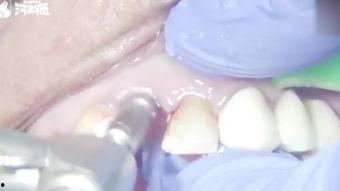

2. 拔除旧门牙:医生会使用专业的工具将旧门牙拔除,这个过程可能会有些不适,但不用担心,麻醉会减轻你的疼痛感。

3. 植入新门牙:拔除旧门牙后,医生会立即植入新门牙。这个过程需要医生有丰富的经验和精湛的技术。